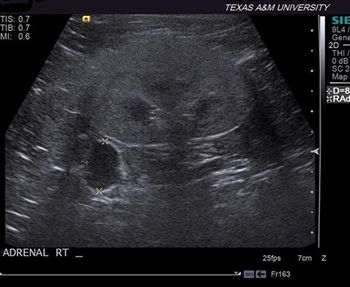

Texas A&M University

A brief review of the diagnosis and treatment of hyperadrenocorticism and the current knowledge on trilostane, including its therapeutic considerations and possible adverse effects.